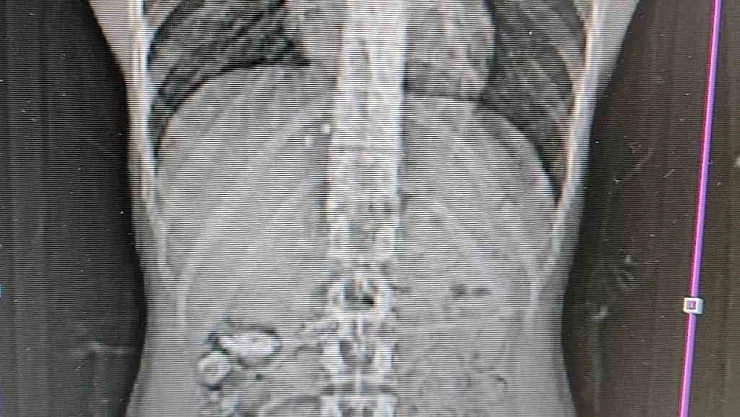

Edinilen bilgilere göre, Gümüşhane İl Emniyet Müdürlüğü’ne bağlı Narkotik Suçlarla Mücadele Şube Müdürlüğü ekipleri tarafından Akçakale Uygulama Noktası’nda durdurulan bir araç içerisindeki yabancı şahsın şüpheli hareketleri üzerine çalışma yapıldı. Uyuşturucu kuryesi olduğu ve yutma suretiyle uyuşturucu taşıdığından şüphelenilen şahsın Gümüşhane Devlet Hastanesi’nde yapılan kontrollerinde, midesinde 18 adet kapsül olduğu tespit edildi. Hastanede yapılan müdahalenin ardından şahsın midesinden çıkarılan kapsüllerin içerisinde toplamda 152,29 gram metamfetamin ele geçirildi.